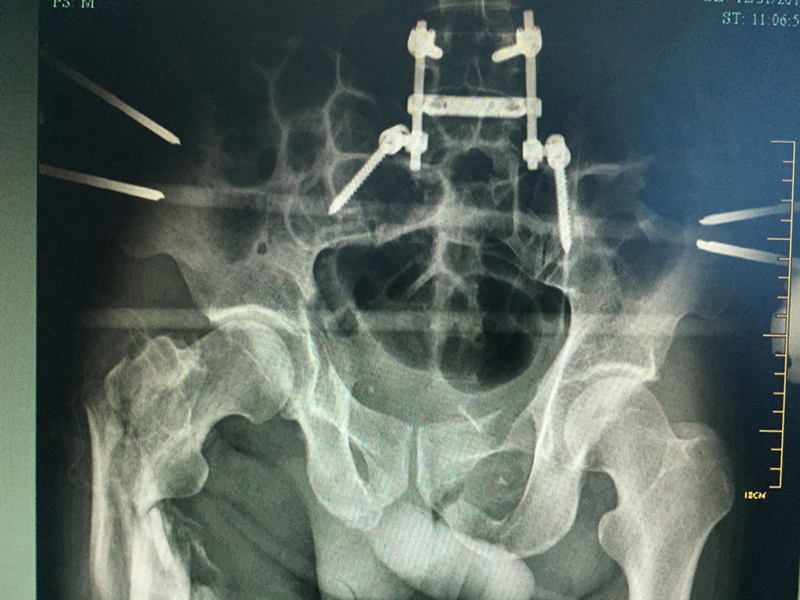

??? 當(dāng)天,張成被轉(zhuǎn)入衢州市人民醫(yī)院救治。到達(dá)衢州市人民醫(yī)院之后,緊張的生命接力就開始了,傷情相當(dāng)嚴(yán)重,張成生命垂危,重癥醫(yī)學(xué)科(ICU)醫(yī)護(hù)團(tuán)隊(duì)立即投入戰(zhàn)斗,進(jìn)行搶救;生命體征一轉(zhuǎn)平穩(wěn),待命的普外科、麻醉科、手術(shù)室醫(yī)護(hù)人員馬上進(jìn)行脾臟切除術(shù);最后把接力棒交給了骨科,方智敏主任會(huì)診后深知這是一個(gè)艱巨的任務(wù),隨即帶領(lǐng)診療組探討治療方案,最終制定了詳細(xì)的診療計(jì)劃,前后對(duì)患者進(jìn)行了三次大手術(shù)……從12月4日至12月31日,短短一個(gè)月的時(shí)間,張成就接受了五次手術(shù)。

??? 患者術(shù)后的部分X影像